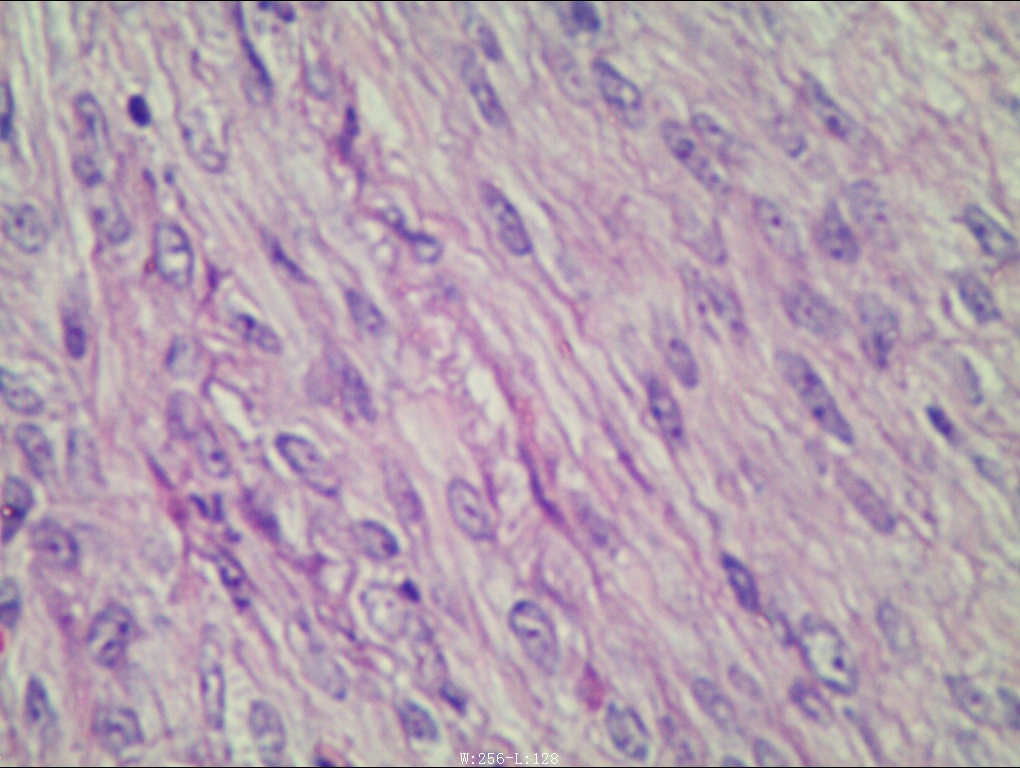

病理诊断:灰白色带蒂结节1枚,直径3cm,蒂直径1.5cm。切面灰白,质韧。另送:灰白色结节状组织19枚,总体积3cm×1.5cm×1cm,直径0.3-1.2cm,切开切面灰白质韧,编织状。瘤细胞长梭形,核杆状,胞质丰富红染,核分裂象罕见。瘤细胞呈编织状、旋涡状排列,部分肿瘤组织玻璃样变。诊断意见:(子宫浆膜下)多发性平滑肌瘤。

好发于30~50岁约占绝经期前妇女的70%~80%肌瘤常为多发,大小不等。发生部位以子宫体最多见。病理表现:子宫肌瘤主要由旋涡状排列的平滑肌细胞构成。肌瘤外表有一层结缔组织束和纤维构成的假性包膜。较大肌瘤由于血供障碍可发生多种变性,包括玻璃样变性、黏液样变性、脂肪样变性等,也可发生坏死、囊变、出血,子宫肌瘤恶变的概率很低,不足1%。